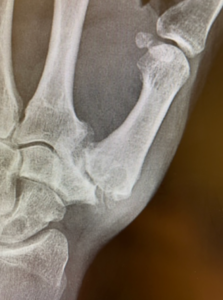

Thumb CMC arthritis occurs when the cartilage that cushions the carpometacarpal joint wears down. The CMC joint connects the thumb metacarpal to the trapezium bone in the wrist. As this cartilage acts as a smooth surface between the bones, degeneration leads to friction, inflammation, and pain.

Patients often describe pain at the base of the thumb, especially when pinching, gripping, or twisting. Over time, the joint becomes enlarged, stiff, and unstable due to lax joint ligaments. The thumb may drift into a crooked or subluxed position.

X-rays reveal narrowing of the joint space, bone spurs, and early cartilage wear. In some cases, mild carpal tunnel symptoms or nerve irritation may also contribute to thumb pain.